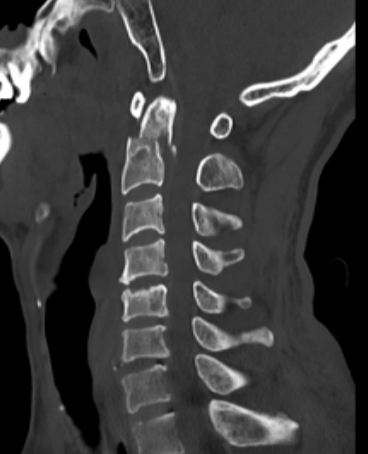

患者劉某某今年50歲,因不慎摔傷導(dǎo)致頸部疼痛、活動受限,并伴有雙側(cè)上肢無力、麻木,到泉港總醫(yī)院做了急診頸椎CT檢查,報告為“樞椎齒狀突骨折伴寰椎椎體后脫位”,隨即收入院治療。

入院后,福建醫(yī)科大學(xué)附屬第一醫(yī)院下派脊柱外科專家朱希田副主任醫(yī)師立即查看了患者的病情,考慮患者樞椎齒狀突骨折伴寰椎后脫位致高位頸脊髓損傷可能性較大,如果不盡早手術(shù),將引起頸脊髓損傷繼續(xù)加重,并可導(dǎo)致高位截癱可能。朱希田副主任醫(yī)師立即將病情匯報醫(yī)院領(lǐng)導(dǎo),開通核磁共振檢查綠色通道,進一步明確患者病情。

朱希田副主任醫(yī)師組織科室醫(yī)護團隊進行了詳細的討論分析,決定先予俯臥位行“后入路寰樞椎骨折切開復(fù)位+椎弓根釘內(nèi)固定術(shù)”,再仰臥位行“前入路頸4-5、頸5-6、頸6-7椎間盤切除+頸椎管減壓+頸椎椎間植骨融合+頸4-頸7椎體鈦板螺釘內(nèi)固定手術(shù)”。

后路寰樞椎內(nèi)固定手術(shù)由于難度大、風(fēng)險高,此前在泉港地區(qū)各醫(yī)院尚未開展該項手術(shù),該例手術(shù)病例為泉港地區(qū)首例。面對時間短、要求高的挑戰(zhàn),朱希田副主任醫(yī)師一方面仔細研究閱讀患者影像學(xué)資料,制定個體化置釘方案,同時積極準備手術(shù)相關(guān)器械,經(jīng)過認真充分的術(shù)前準備,患者于入院后第3天進行手術(shù)。

憑借嫻熟的手術(shù)技術(shù),醫(yī)生成功地在復(fù)雜的寰樞椎上置入椎弓根螺釘,并將脫位的齒狀突骨折和寰椎完全復(fù)位,成功實現(xiàn)了精準置釘和完全復(fù)位,且手術(shù)創(chuàng)傷小,出血少,在小切口下順利完成;前路多節(jié)段頸椎手術(shù)也很順利,前路+后路手術(shù)出血僅100-200ml。術(shù)后患者很快恢復(fù)清醒,四肢開始活動,術(shù)后8小時開始進流質(zhì)飲食,術(shù)后第3天便可下地行走,之后各項生活逐漸恢復(fù)自理。